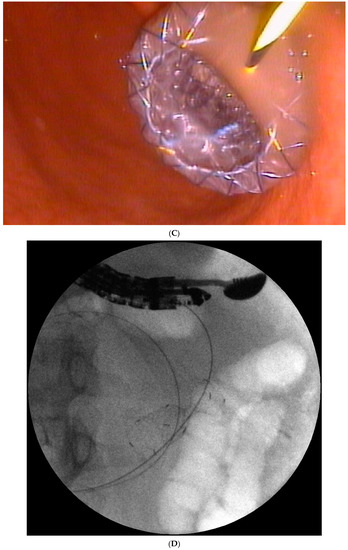

Figure 1. (A–L) Endoscopic treatment of walled-off pancreatic necrosis. In the second week of acute necrotizing pancreatitis, the acute necrotic collection (A) is visible in the abdominal contrast-enhanced computed tomography (CECT), which evolved in the sixth week of the illness duration into the symptomatic walled-off pancreatic necrosis (B). Patient qualified for endoscopic treatment (C–F) transmural drainage using the self-expanding metal stent (C,D) and endoscopic necrosectomy (E,F) was performed. In the second week of endotherapy, the endoscopic retrograde pancreatography (G–J) was performed. During pancreatography, the complete pancreatic duct disruption was stated (G–I) and transpapillary drainage was carried out (J). After achieving the treatment’s success and the complete regression of the necrotic collection, the transpapillary stent was observed in the bottom of the collection via the endoscopic view from the stomach’s side through the transmural stent (K). Control CECT confirmed the total regression of the collection (L).